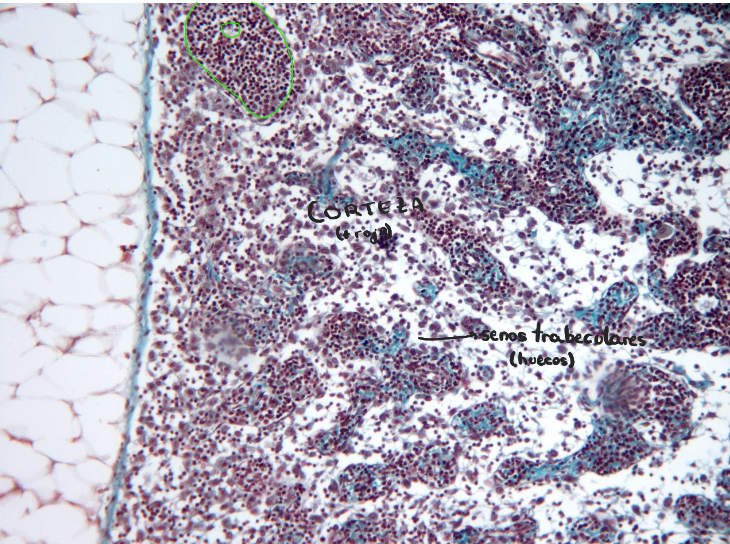

Estructura ganglio linfático

Ganglio linfático

Corteza:

externa - folículos linfáticos

interna - tej linfoide difuso + vénulas del endotelio alto

fibras reticulares del estroma - verde

en verde - folículo linfático secundario con su centro germinativo